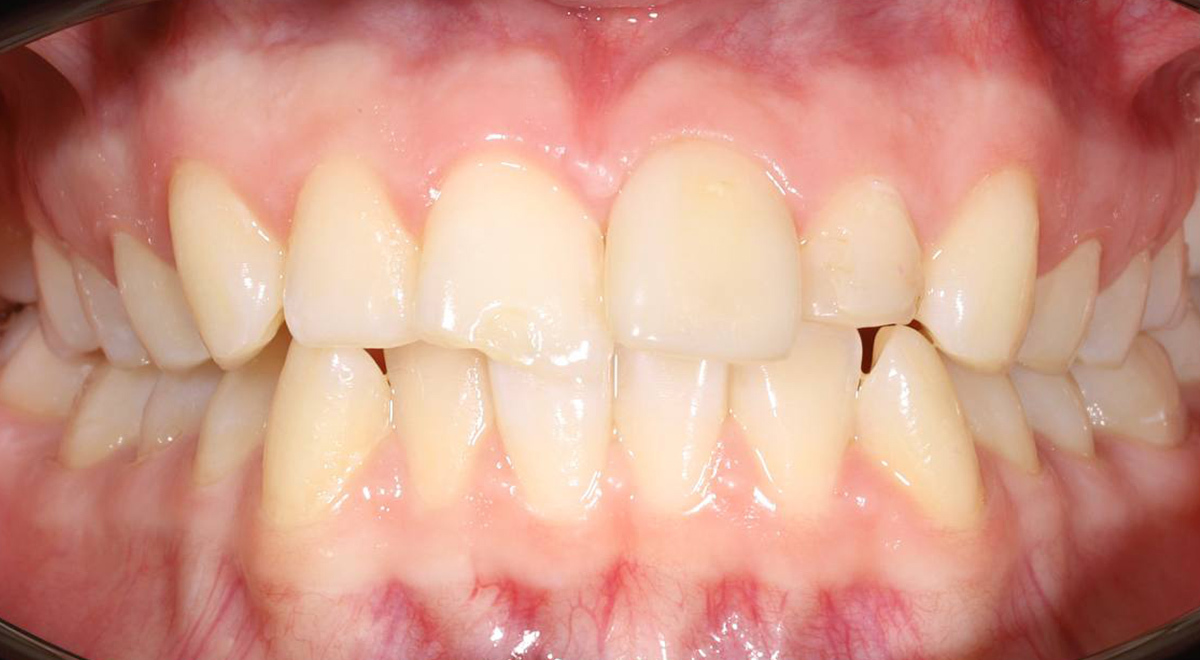

Выравнивание скученных зубов и исправление прикуса на самолигирующих брекетах